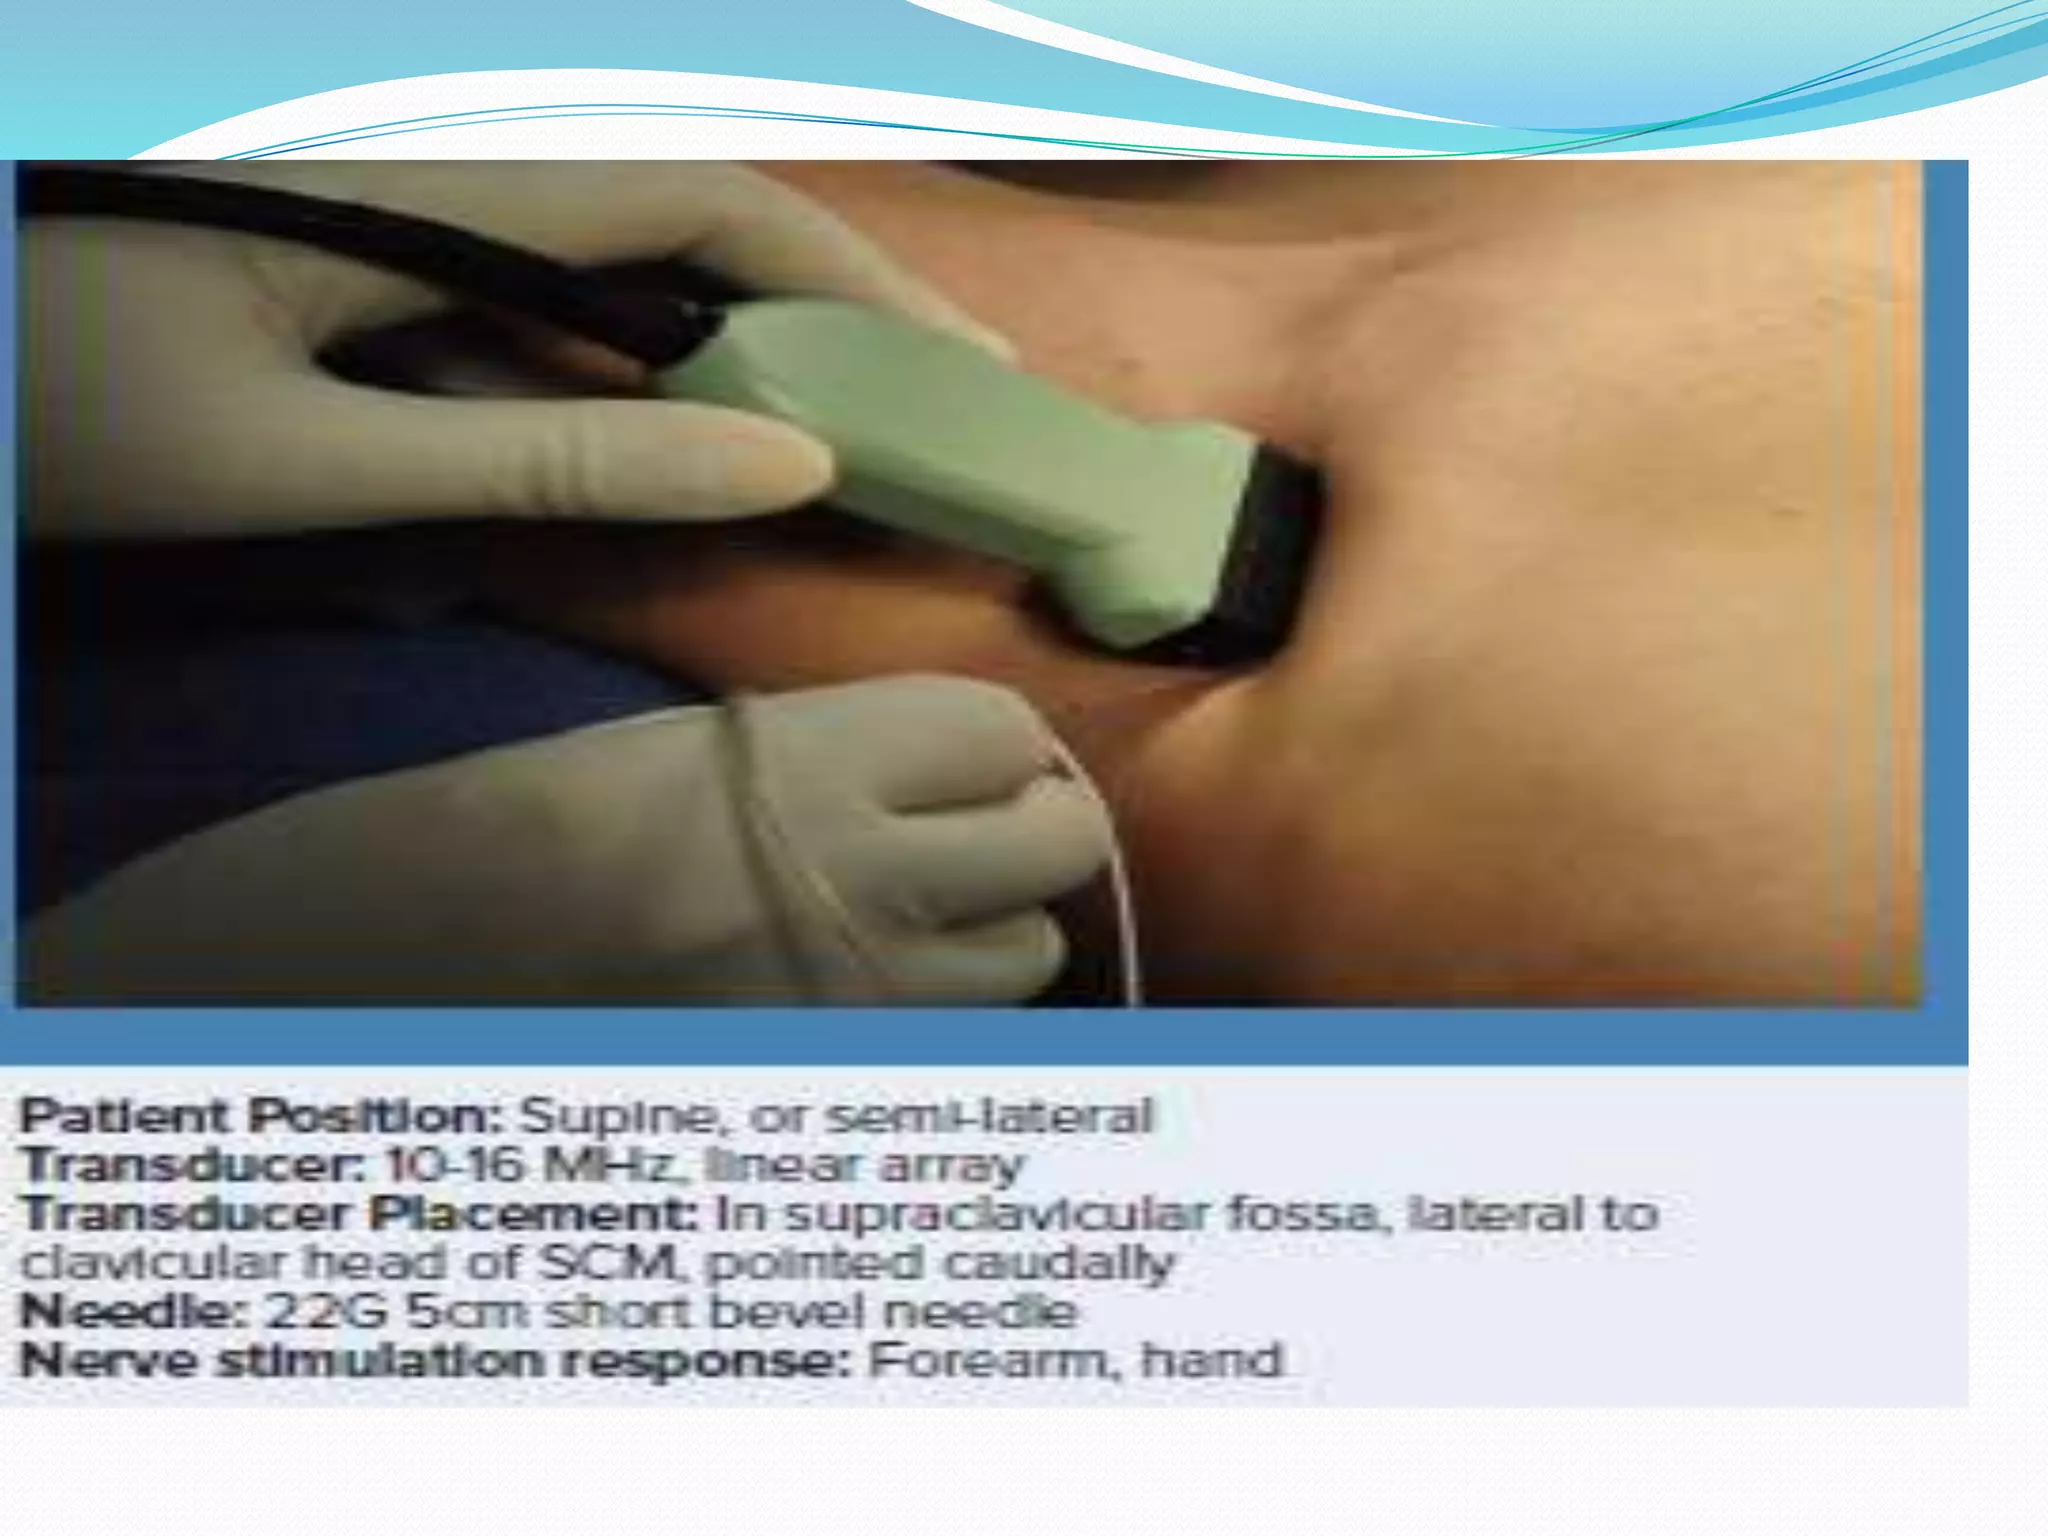

This document provides an overview of brachial plexus anatomy and techniques for brachial plexus nerve blocks. It begins with a description of the brachial plexus formation from cervical and thoracic nerve roots and its branching pattern. Four main approaches for brachial plexus nerve blocks are described: interscalene, supraclavicular, infraclavicular, and axillary. Details are provided on the anatomy and techniques for performing interscalene and supraclavicular brachial plexus blocks. Ultrasound guidance is discussed as an advancement which allows real-time visualization of needle and nerve. Complications are also summarized.